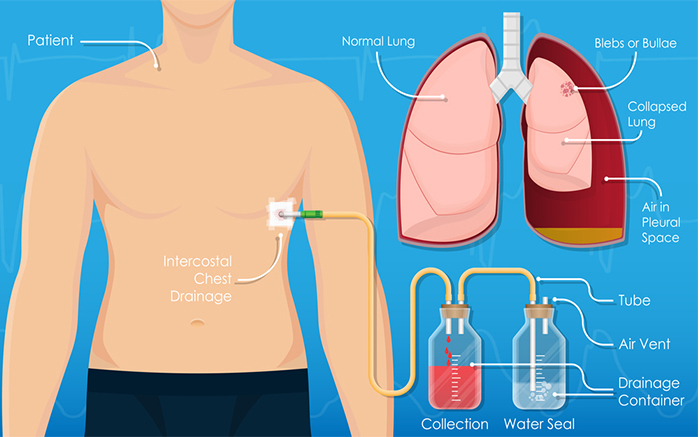

Specialist in Tuberculosis, Asthma, COPD, ILD, Pneumonia, Allergy, Bronchoscopy, Chest Diseases, Critical Care, and Sleep Disorders.

Dr. Gyanendra Shukla is a distinguished medical professional with a stellar academic background and significant expertise in pulmonary medicine. He obtained his MBBS degree from the esteemed Madurai Medical College, followed by post-graduation in respiratory medicine from the prestigious National Institute of Tuberculosis and Respiratory Diseases in New Delhi.